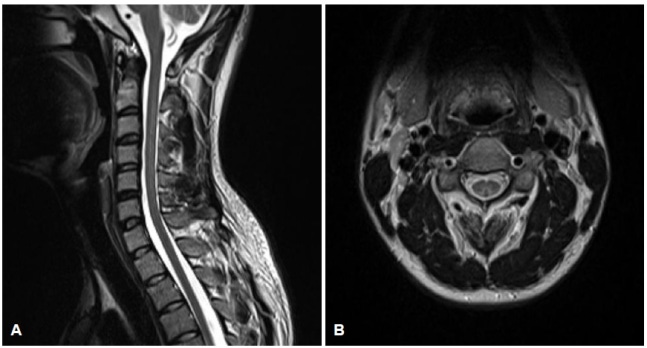

해피벌룬을 남용하다가 척수신경병에 걸린 20대 남성의 척수 MRI 영상. 대한신경과학회지

검사 결과 A씨에게서 아산화질소 과량 흡입에 의한 비타민 ‘B12’의 감소가 확인됐다. 비타민 B12가 부족해지면 빈혈과 신경계 이상이 생길 위험이 높아진다. 아산화질소는 신경계 독성을 일으키는 치명적인 부작용도 있다. 비타민 B12의 감소는 ‘메틸말론산’이라는 물질의 대사도 억제해 혈중농도를 높이고 척수병 위험을 높인다.

의료진은 ‘비타민 B12 결핍에 의한 척수신경병’으로 진단하고 비타민 B12를 매일 1㎎식 근육주사로 1주일 투약하고 이후 주 1회 간격으로 2개월간 주사 치료를 계속했다. 그 뒤에는 먹는 비타민으로 변경해 치료했다. 치료를 받은 지 1개월 뒤부터 감각 저하가 점점 나아지기 시작했고 무려 3개월이 지나서야 감각이상, 소변장애, 발기부전 증상이 치료됐다. 연구팀은 “최근에 아산화질소가 ‘해피벌룬’이라는 이름으로 젊은 세대에게 쉽게 노출돼 환각제로 남용되고 있다”며 “이번에는 처음으로 척수병과 연관된 발기부전까지 보고됐다”고 밝혔다.